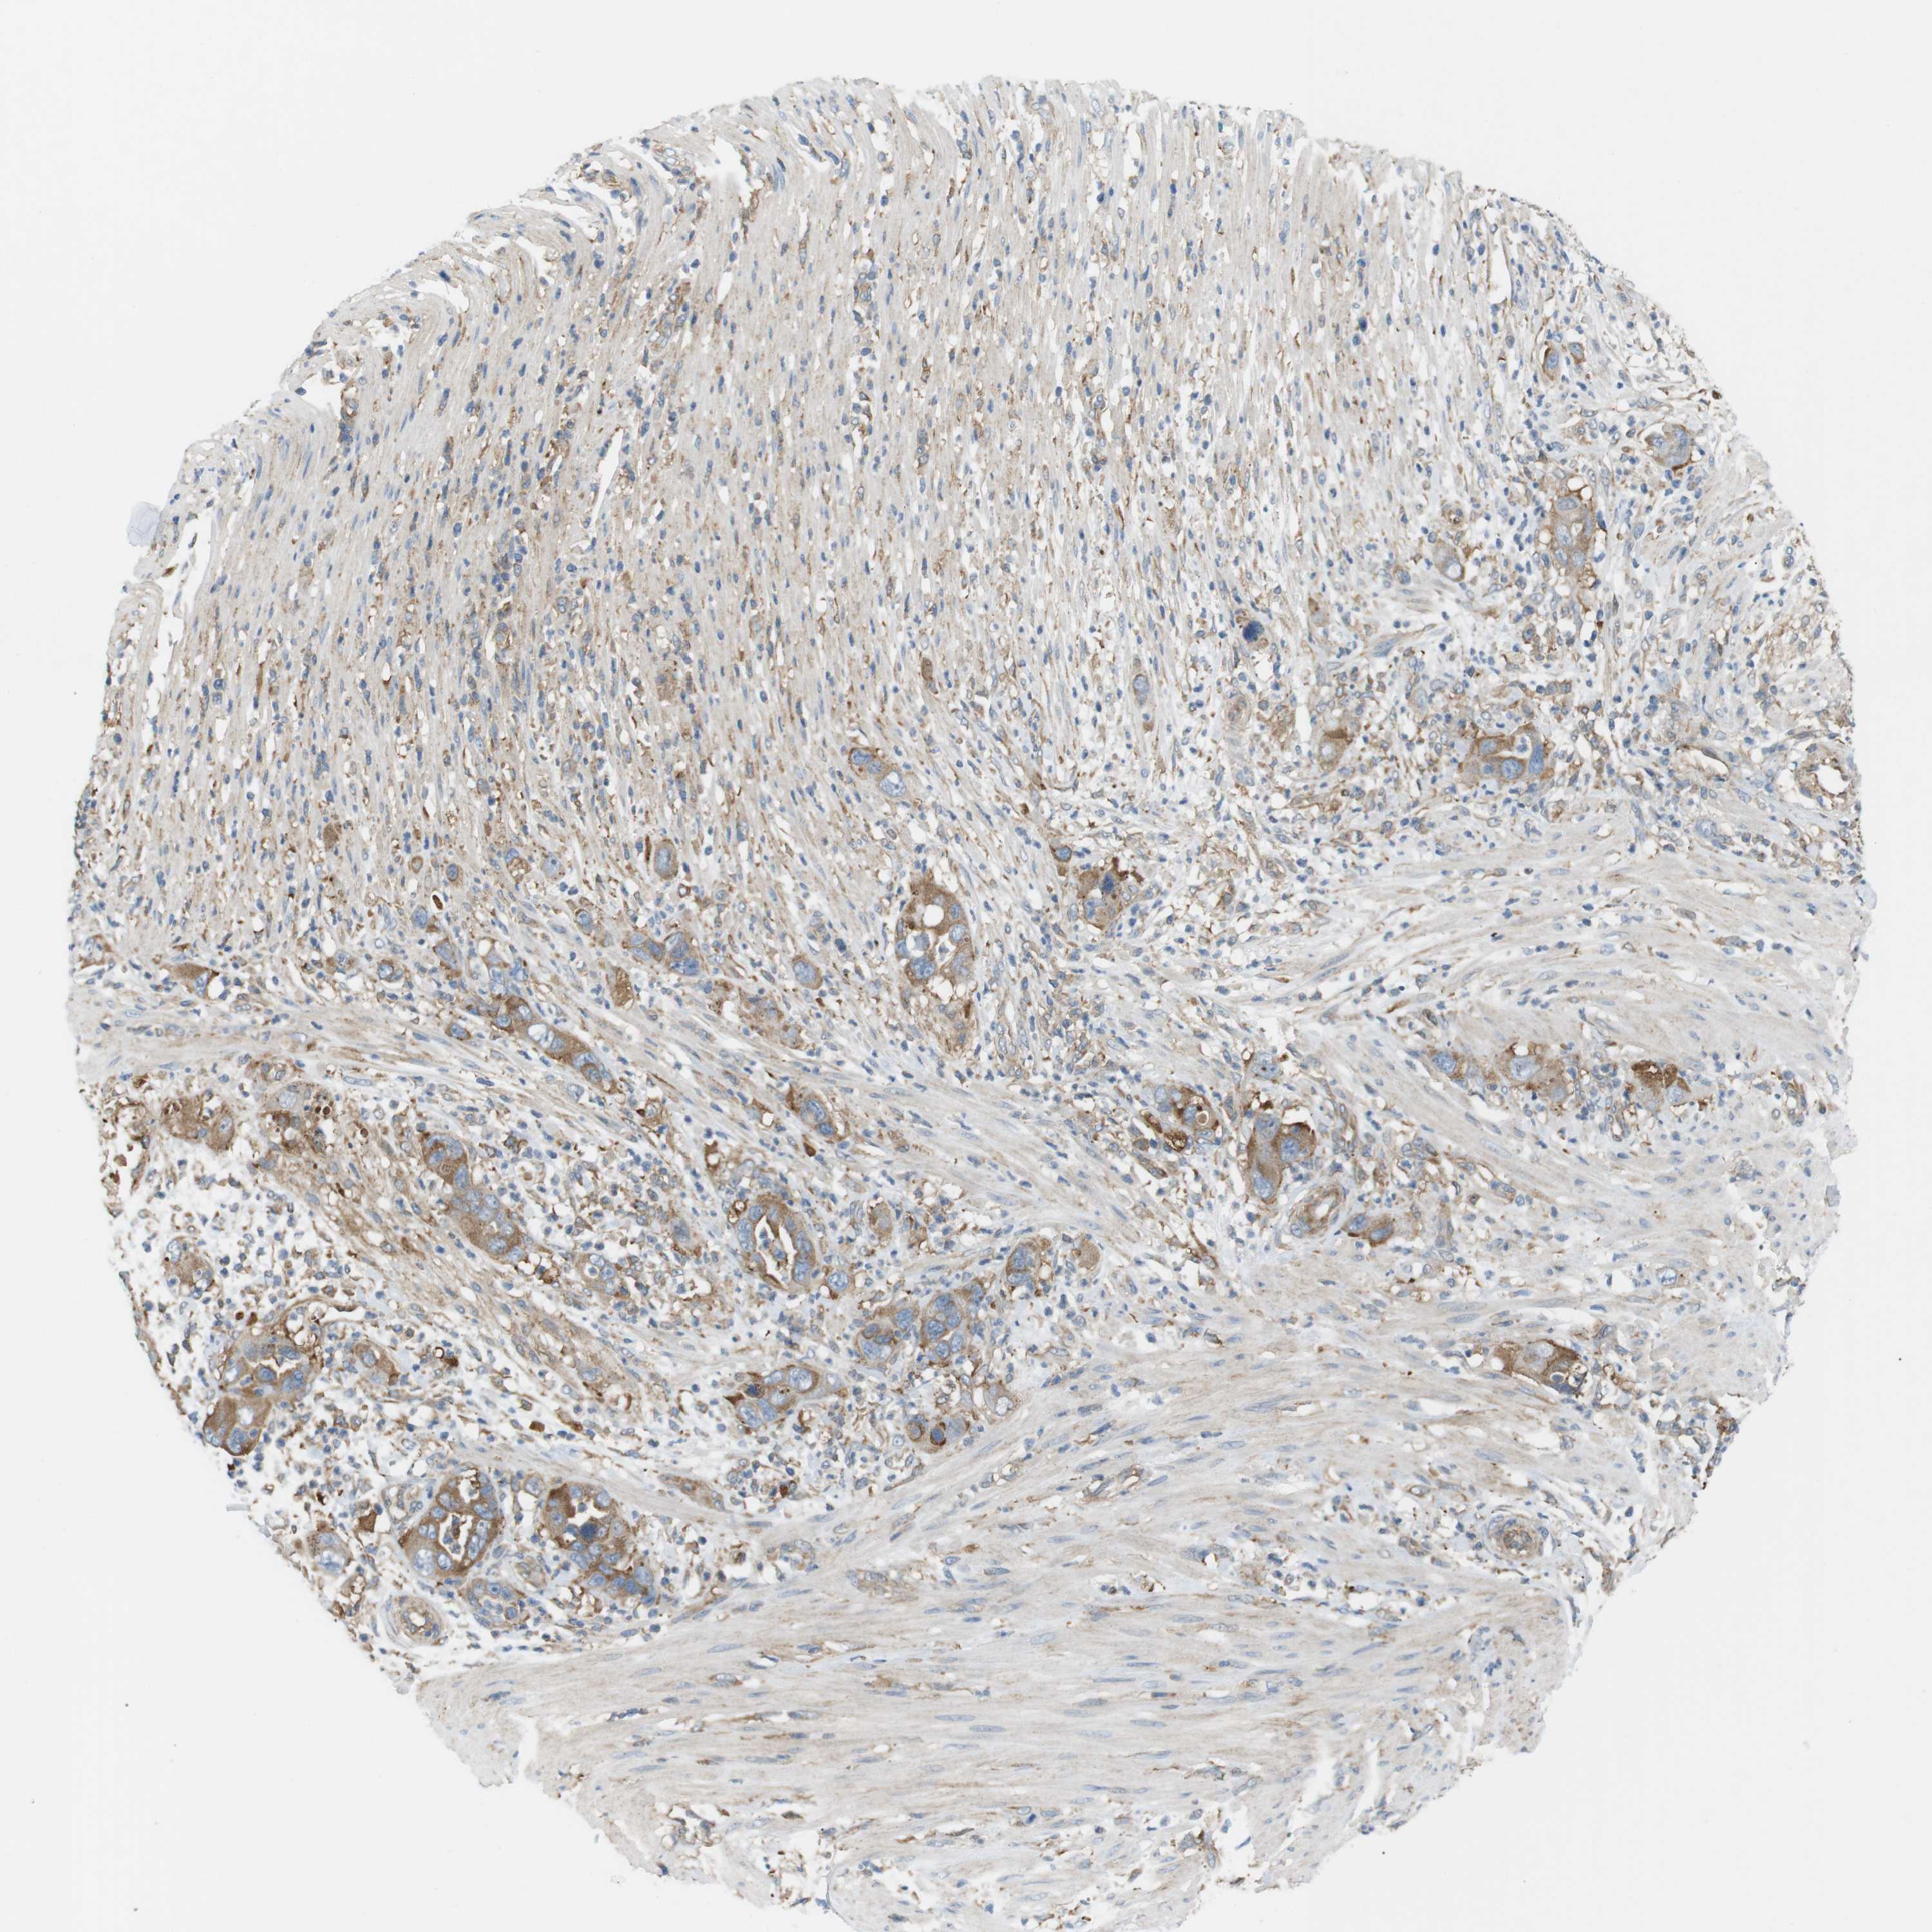

PANCREATIC CANCER - Protein expressioni

A mouse-over function shows sample information and annotation data. Click on an image to view it in a full screen mode. Samples can be filtered based on level of antibody staining by selecting one or several of the following categories: high, medium, low and not detected. The assay and annotation is described here.

Note that samples used for immunohistochemistry by the Human Protein Atlas do not correspond to samples in the TCGA dataset.

Antibody stainingi

Antibody staining in the annotated cell types in the current human tissue is reported as not detected, low, medium, or high, based on conventional immunohistochemistry profiling in selected tissues. This score is based on the combination of the staining intensity and fraction of stained cells.

Each image is clickable and will lead to virtual microscopy that enables deeper exploration of all samples and also displays staining intensity scores, fraction scores and subcellular localization as well as patient and tissue information for each sample.

Antibody HPA015599

Staining

High

Medium

Low

Not detected

Intensity

Strong

Moderate

Weak

Negative

Quantity

>75%

75%-25%

<25%

None

Location

Nuclear

Cytoplasmic/membranous

Cytoplasmic/membranous,nuclear

Adenocarcinoma, NOS